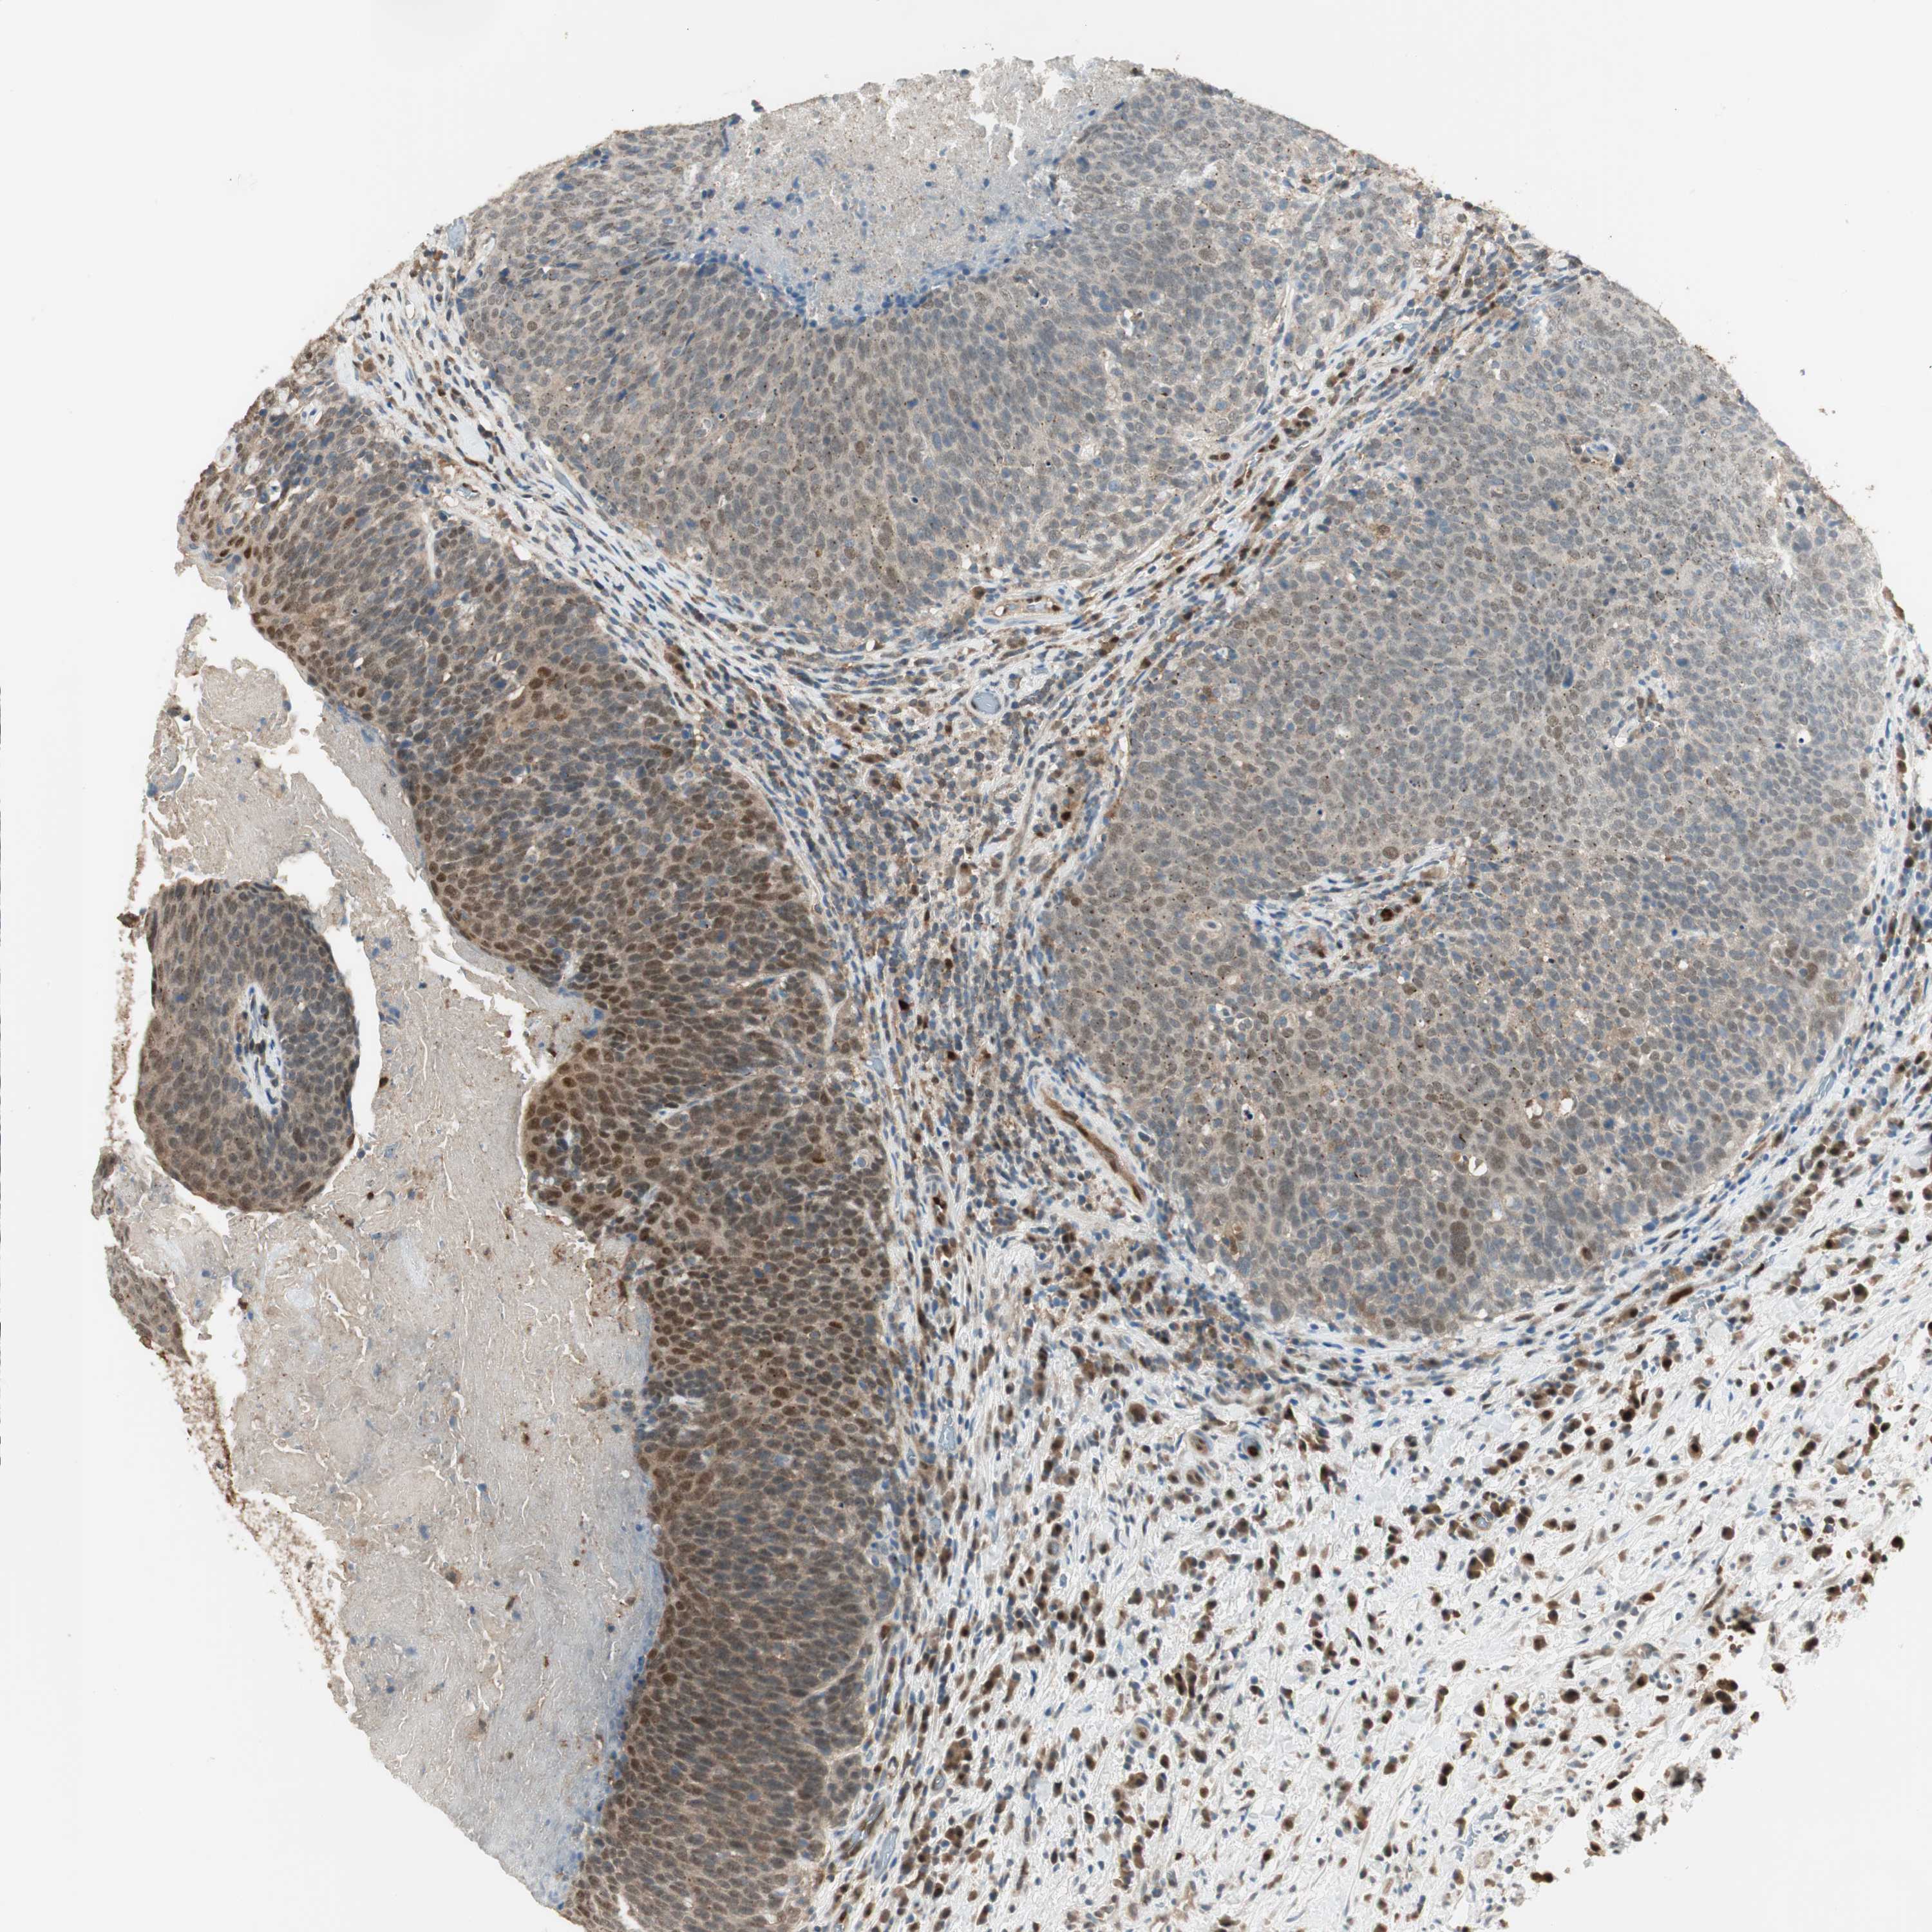

HEAD AND NECK CANCER - Protein expressioni

A mouse-over function shows sample information and annotation data. Click on an image to view it in a full screen mode. Samples can be filtered based on level of antibody staining by selecting one or several of the following categories: high, medium, low and not detected. The assay and annotation is described here.

Antibody stainingi

Antibody staining in the annotated cell types in the current human tissue is reported as not detected, low, medium, or high, based on conventional immunohistochemistry profiling in selected tissues. This score is based on the combination of the staining intensity and fraction of stained cells.

Each image is clickable and will lead to virtual microscopy that enables deeper exploration of all samples and also displays staining intensity scores, fraction scores and subcellular localization as well as patient and tissue information for each sample.

Antibody HPA008399

Antibody HPA017017

Antibody CAB015221

Staining

High

Medium

Low

Not detected

Intensity

Strong

Moderate

Weak

Negative

Quantity

>75%

75%-25%

<25%

None

Location

Nuclear

Cytoplasmic/membranous

Cytoplasmic/membranous,nuclear

Squamous cell carcinoma, NOS

Squamous cell carcinoma, metastatic, NOS

Adenocarcinoma, NOS

Adenoma, NOS